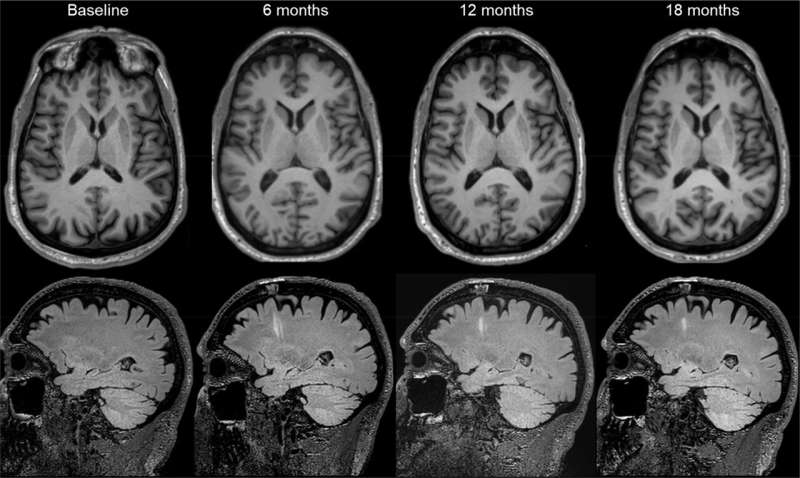

代表性磁共振圖像。圖片來(lái)源:《自然》(2025)。DOI:10.1038/s41586-025-08845-y

第二項試驗在美國和加拿大各地進(jìn)行,Viviane Tabar及其同事探究了源自人類(lèi)胚胎干細胞的多巴胺能神經(jīng)元祖細胞產(chǎn)品(bemdaneprocel)的安全性。12名患者(平均年齡67歲)接受了手術(shù),將bemdaneprocel移植到大腦兩側的殼核。5名參與者接受了低劑量(每核0.9百萬(wàn)個(gè)細胞),7名參與者接受了高劑量(每核2.7百萬(wàn)個(gè)細胞)。

該細胞產(chǎn)品總體耐受性良好,在18個(gè)月的隨訪(fǎng)期內未報告與治療相關(guān)的嚴重不良事件。此外,未出現此前用于治療帕金森病的胎兒組織移植相關(guān)運動(dòng)障礙的發(fā)生。